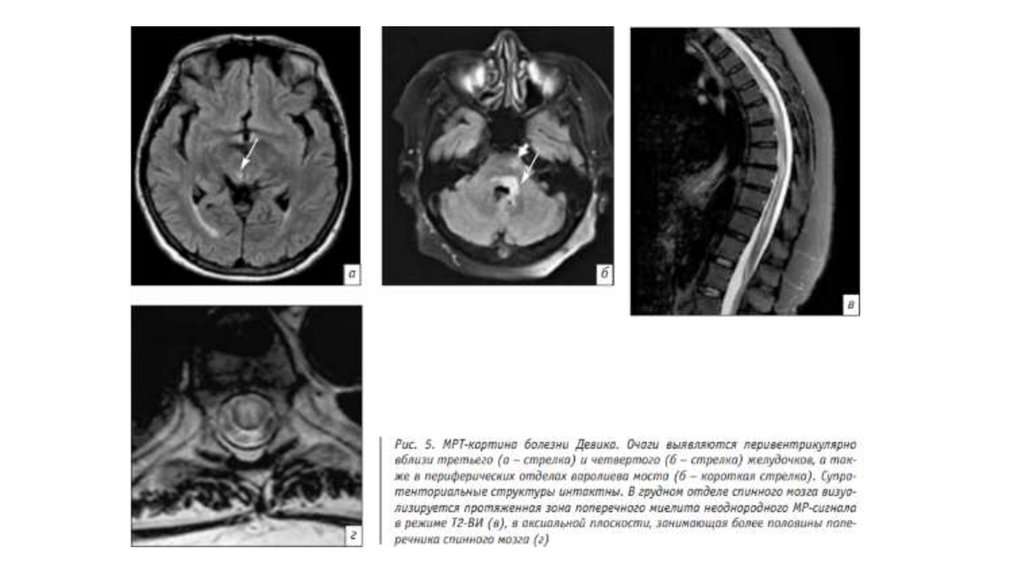

К характерным МРТ-признакам относятся наличие очага демиелинизации в прехиазмальных

отделах зрительных нервов и протяженных (более двух сегментов спинного мозга) очагов

поперечного миелита, преимущественно в грудном отделе позвоночника. При этом очаги и

соответствующая симптоматика в большинстве случаев появляются не одновременно. При

болезни Девика очаги в спинном мозге отличаются от таковых при РС

длинносегментарностью, в аксиальной плоскости они занимают более половины поперечника

спинного мозга, имеют более высокий сигнал на Т2-ВИ, приближаясь к интенсивности

ликвора, а также тропны к грудному отделу в отличие от РС, для которого более характерно

поражение шейных сегментов на начальных стадиях. Наряду с изменениями в зрительных

нервах и спинном мозге также возможно обнаружение очагов в головном мозге,

преимущественно локализующихся вокруг третьего, четвертого желудочков и водопровода

мозга в соответствии с наибольшей плотностью расположения рецепторов к аквапорину-4, а

также в таламусе и гипоталамусе.

Характерным является поражение дорсальных отделов продолговатого мозга (area postrema),

чем и объясняется симптоматика в виде тошноты и рвоты. Кроме того, на МРТ

визуализируются односторонние или двусторонние очаги в глубоких и субкортикальных

отделах белого вещества полушарий большого мозга, а также протяженное поражение

мозолистого тела